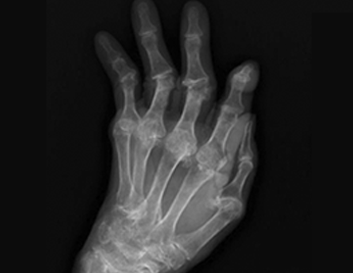

• 손가락 마디 · 손목

류마티스 관절염 · 주관증후군 · 퇴행성 관절염

· 손목 터널 증후군 · 손저림 . 방아쇠수지